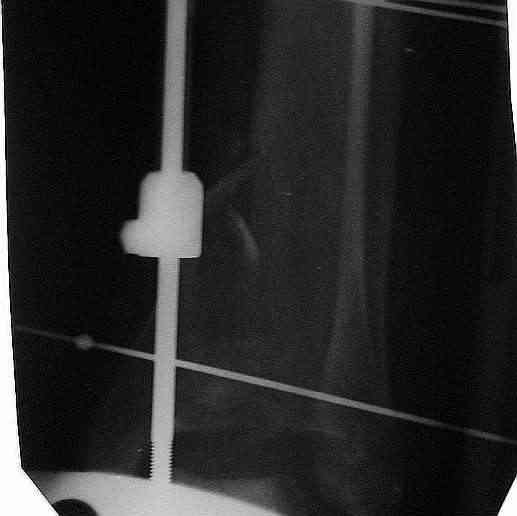

Вчера (прошло около 8 месяцев)больной обратился ко мне в очередной раз с жалобами на боли умеренно-жгучего характера в области выстояния концов болта-стяжки. На момент осмотра:укорочение левой нижней конечности на 1,5 см; гипотрофия медиальной группы мышц голени и четырехглавой мышцы бедра; передвигается без дополнительной опоры в ортопедической обуви на растояние до 5 км; работает приемщиком цветных металлов (приходится перетаскивать грузы). Нарентгенограмме, насколько это можно видеть, костного блока сформировать не удалось, но движений в голеностопном суставе нет - ни активных, ни пассивных. Послеоперационные рубцы б/о; свищей и нагноения не было. Активно больногонаблюдать не приходилось, т.к. проживает в другом городе.

придется удалить.Как правило,если уж пошла миграция металла,то либо ломается, либо нагнаивается. После удаления болта может появиться подвижность в суставе-при несостоятельности артродеза-и усиление болей.

В этом случае возможно предпринять корригирующую остеотомию большеберцовой- выше места перелома и повторно артродез в аппарате. Необходим тщательный контроль больного- спицевые нагноения чаще всего у недисциплинированных, плохо контролируемых пациентов.